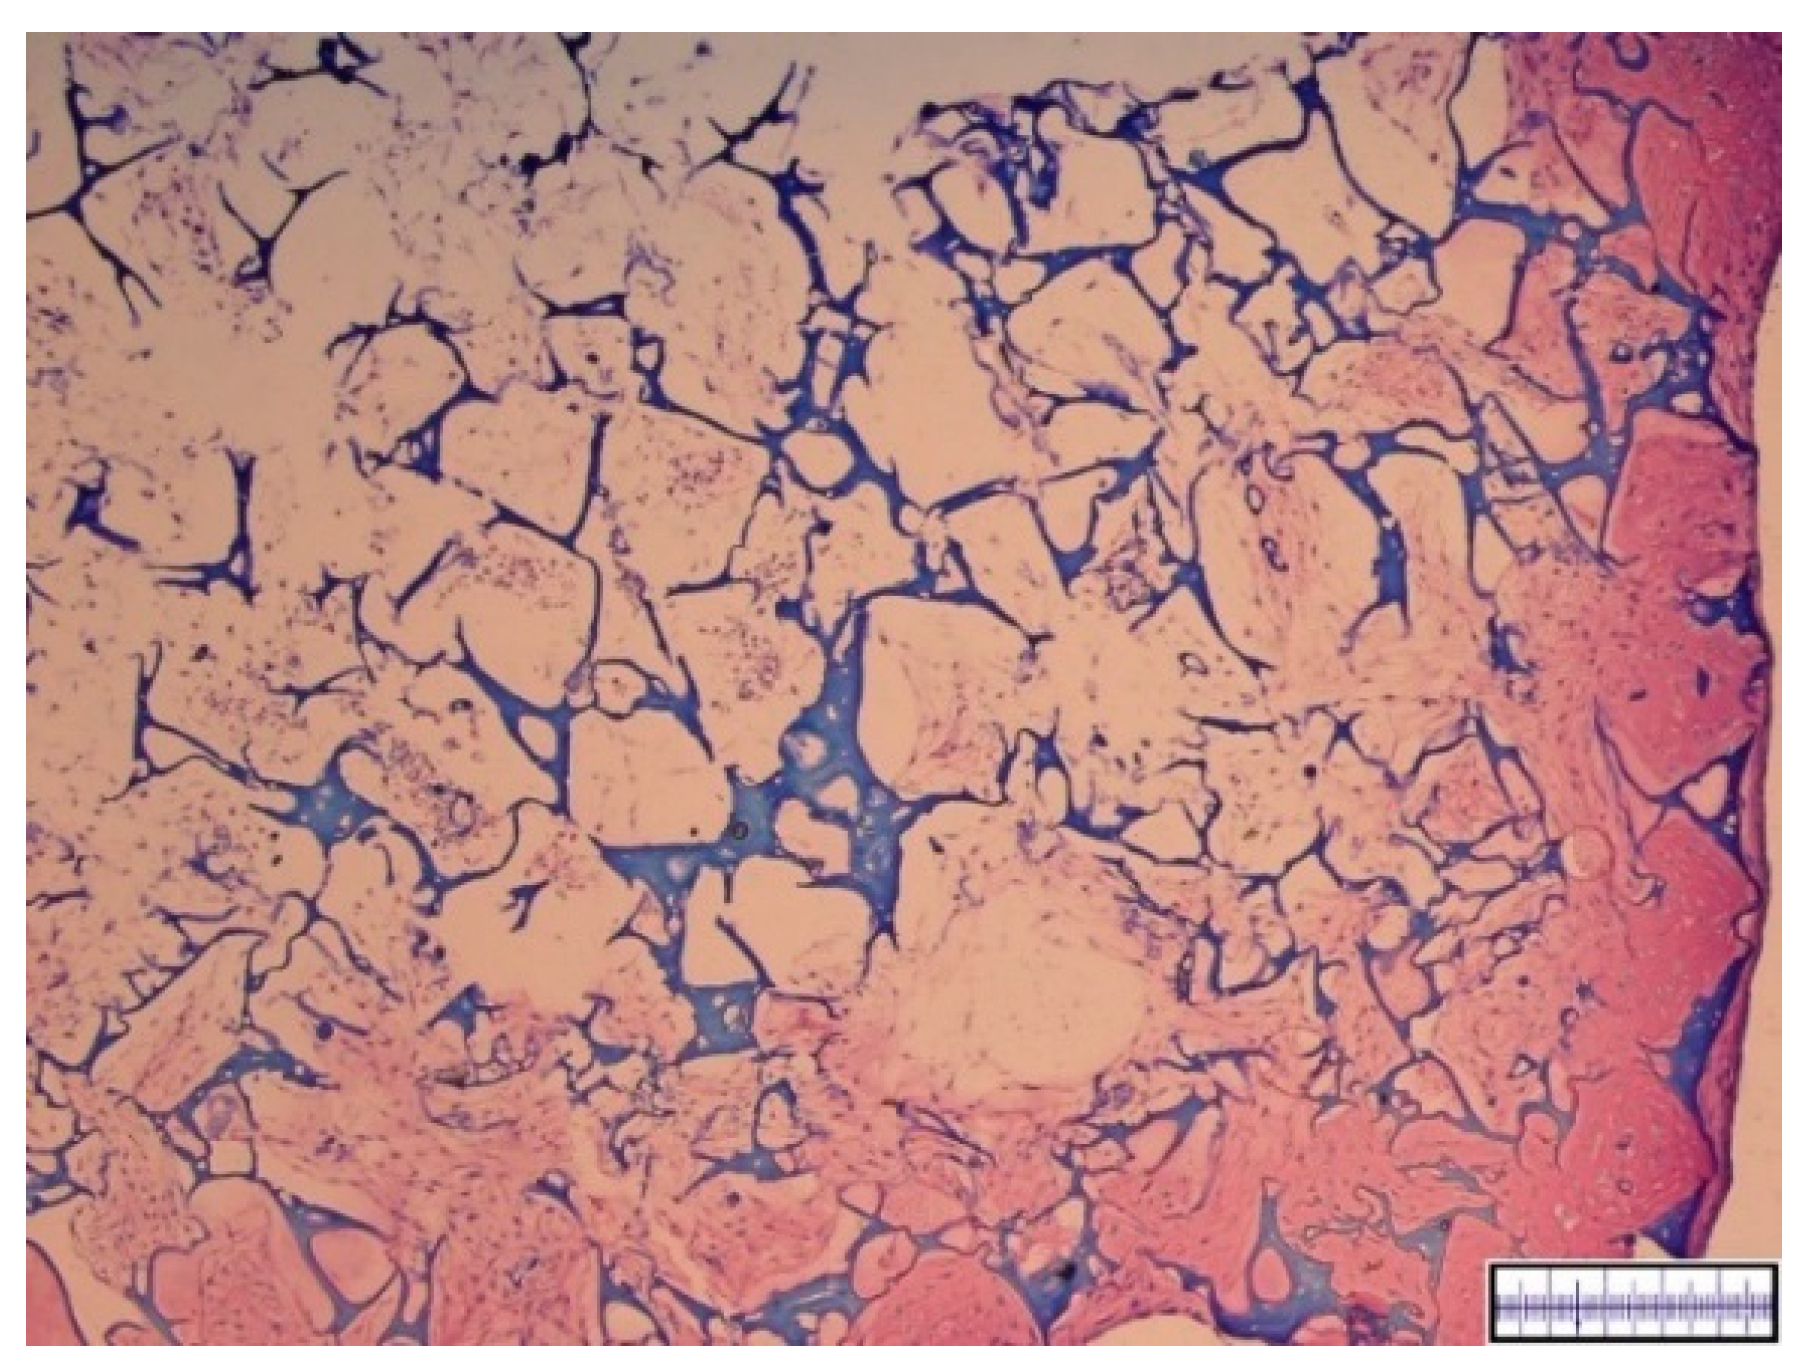

3.1. Macroscopical Assessment of Scaffold Pore Structure

3.2. Interconnectivity of Scaffold Pores